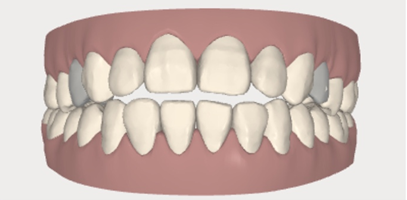

已经做好了被塞满口橡皮泥一样的东西做模型了,黄医生拿出一个手持微型扫描仪一样的东西,说,“张开嘴现在我来取一下你牙齿的模型”。我心里咯噔,这是什么高科技,一边乖乖的看着黄医生的仪器在我嘴里一边移动一边咔咔咔的连续照相,我的牙齿就这样一点一点的出现在了旁边的屏幕上!感觉羞愧又神奇!不到五分钟,屏幕上就有了我完整的牙齿模型,包括咬合位置。下图是我的3d牙齿模型正面和侧面截图,阴影的那两颗牙是我决定拔掉的两颗牙。

偷拍的高科技扫描仪,黄医生说不仅更舒适精确度也大大大提升哦!扫描完之后就会有一个完整的牙齿模型,和非常非常粗略的预期矫正效果。黄医生会根据你的预期,在咬合正确的最大程度上实现美观,不仅是牙齿,还有脸型的要求,来设计一个精确的,完整的方案。

视频不好放我就放个前后对比吧,阴影部分是矫正前,白色部分是矫正完成(33副牙套)后的效果。我伙呆!请收下我的膝盖!

看完整个动图之后我虽然很开心,但是还是满心疑惑,我的牙齿真的会变成这样吗?是怎么做到的呢?